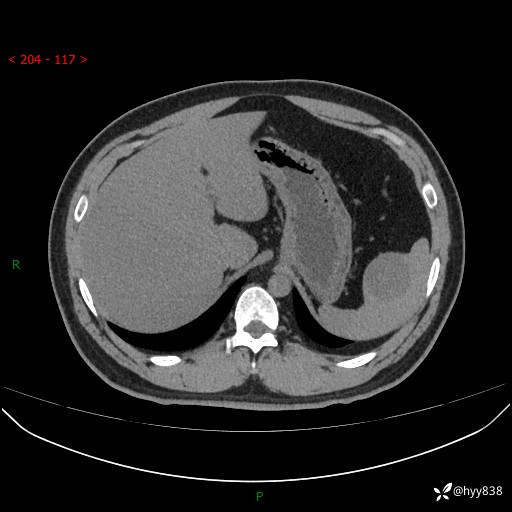

【患者信息】:31岁/男

【主诉】:超声发现脾脏肿物,为进一步诊治来我院,门诊以“脾脏占位”收入院

【检查】:上腹部CT平扫+增强